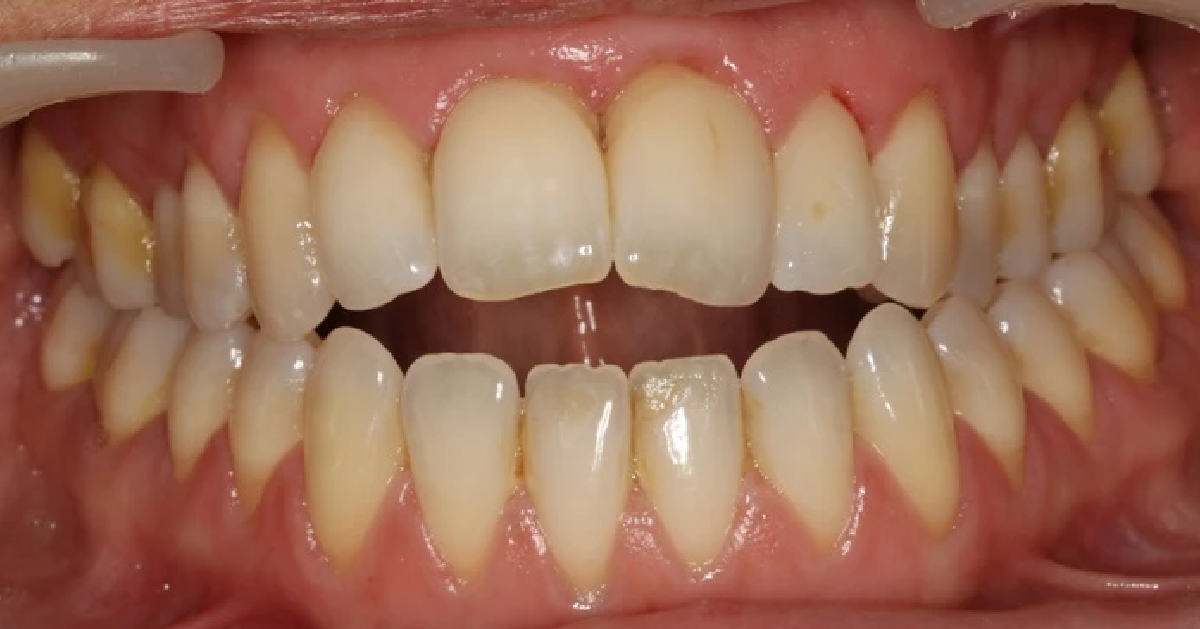

Vårt arbeid

Alle pasienter som vises har gitt skriftlig samtykke til at bildene kan brukes på klinikkens nettside.

Ønsker du en vurdering av behov for tannregulering, kan du ta kontakt med klinikken for time til konsultasjon.